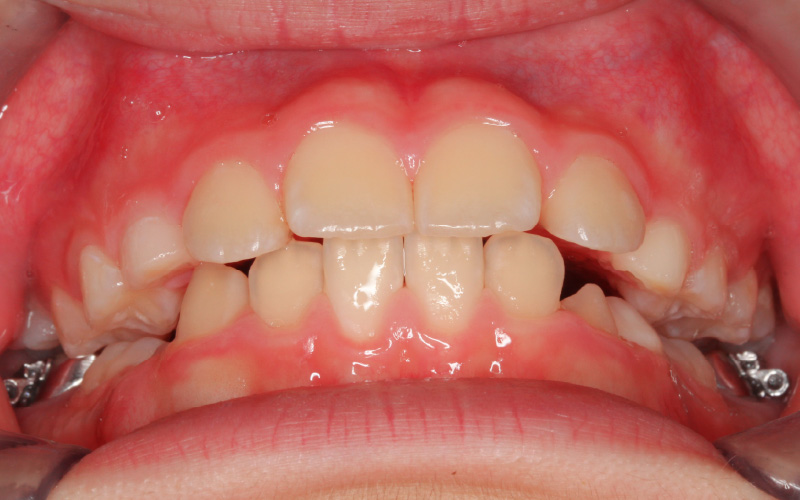

スプリント後

[13歳4か月/矯正治療開始時]

初診から約2年経過し、乳歯も萌え変わり永久歯列となったため、記録を採り成長の様子を観察しました。

スプリントの夜間装着によって、下顎の位置が安定してきました。下顎はバランス良く大きく成長し、咬合平面の右上がりの傾斜も改善しています。MRIにより下顎の成長がアクティブな状態を観察できたので、矯正治療をスタートしました。